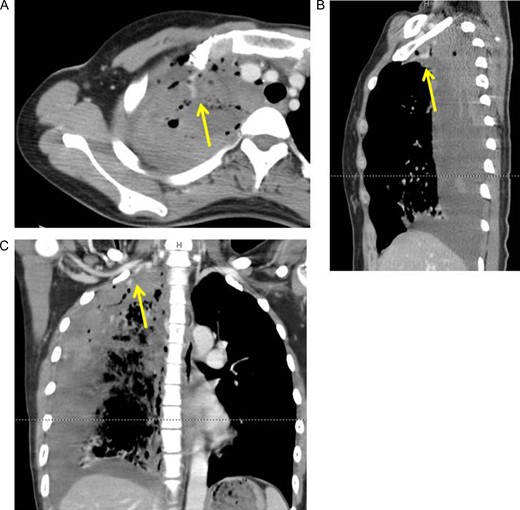

However, 2 h after the drainage, tachypnea and shock vitals (blood pressure: 78/60 mmHg, heart rate: 120/min) were identified. Repeated chest X-ray revealed an increase in the amount of right pleural fluid. The hemoglobin level of the blood from vessel decreased to 6.4 mg/dl. Contrast-enhanced CT was performed. It revealed extra-vascular signs at the top of the right pleural cavity (Fig. 2A–C).

Axial (A), sagittal (B) and coronal (C) view of contrast-enhanced computed tomography revealed extra-vascular signs (arrows) on top of the right pleural cavity.

Absolute hemostasis is required in surgery. The most common etiology of bleeding in SHP is the tearing of aberrant vessels between the parietal pleura and adhesion bulla due to lung collapse for pneumothorax [7, 8]. Such aberrant vessels often lack a sphincter muscle, and negative intrapleural pressure may encourage continuous massive bleeding [8]. Although other sources of bleeding, such as a torn parietal pleura, ruptured vascularized bullae or lung parenchyma, have been reported [4, 5, 7, 8], in 29.6–35% cases, the origin of bleeding cannot be identified [8]. In our case, the extra-vascular signs on enhanced CT were very useful in helping us decide to perform an emergency operation and for detecting the bleeding point. Because the bleeding point was identified preoperatively, we easily found the origin of the bleeding and achieved hemostasis by clipping via VATS.